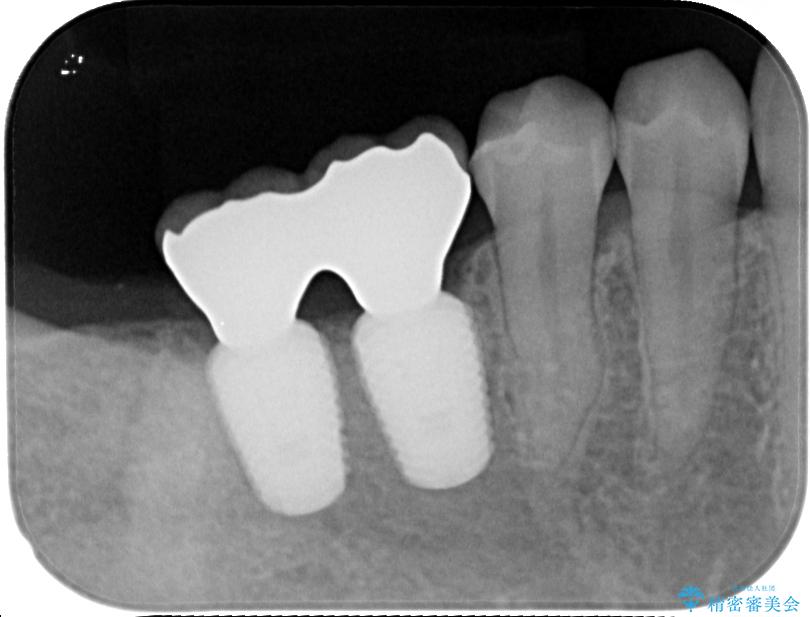

スペースが整った段階で、右下の第一大臼歯と第二大臼歯にインプラントを埋入。

• 挺出歯を圧下してスペースを確保!目立たない部分矯正で下顎大臼歯にインプラント治療を実現 治療途中画像